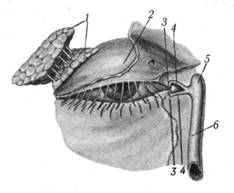

Слезный аппарат (apparatuslacrimalis) каждого глаза включает слезную железу и слезовыводящие пути.

Слезная железа (glandulalacrimalis) (рис.2.5) расположена в одноименной ямке верхненаружного угла глазницы, имеет небольшие размеры (2,5 X 1,2 см), и выводные протоки ее (в количестве 5 - 12) открываются в области верхнего свода конъюнктивального мешка. Слезная железа выделяет прозрачную бесцветную жидкость — слезу (lacrima), которая предохраняет глаз от высыхания.

Из конъюнктивального мешка омывшая глаз слезная жидкость (часть ее испаряется) скапливается у внутреннего угла глазной щели вблизи слезного мясца, где образуется так называемое слезное озеро. Отсюда через точечные отверстия (верхнее и нижнее) слезная жидкость поступает в два слезных канальца, вливающиеся в слезный мешок (saccuslacrimalis), залегающий в соответствующей ямке медиальной стенки глазницы (рис.2.5). Нижний конец слезного мешка непосредственно переходит в носо-слезный проток, открывающийся в нижний носовой ход.

Рис.2.5. Слезный аппарат:

1 — слезная железа; 2 — хрящ верхнего века; 3 — слезные точки; 4 — слезные канальцы; 5 — слезный мешочек; 6 — носо-слезный проток.